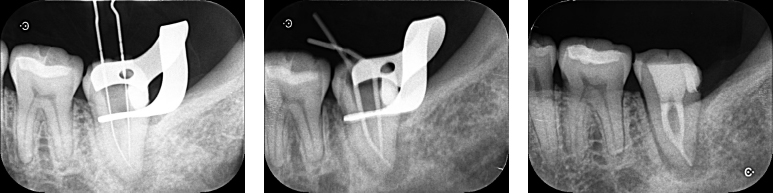

根管は根の先端部分で合流しており、マイクロスコープを使用して徹底的に根の中の清掃を行いました。やや特殊な形状でしたが、根管充填も問題なく完了し、次回は6ヶ月後の経過観察となりました。

| 根管洗浄 | 次亜塩素酸ナトリウム溶液・EDTA溶液 |

| 根管貼薬 | 水酸化カルシウム |

| 拡大号数 | M根#40/04 D根#50/04 |

| 根管充填 | バイオセラミックシーラーを用いたHydraulic condensation technique |